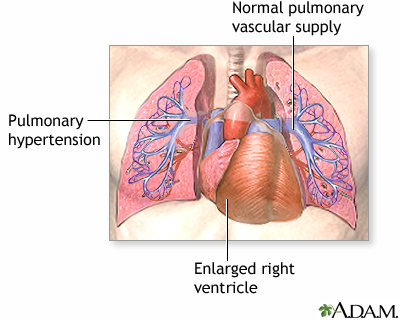

Pulmonary hypertension is high blood pressure in the pulmonary arteries of the lungs. It makes the right side of the heart work harder than normal.

The right side of the heart pumps blood into the pulmonary artery and then through the lungs, where it picks up oxygen. Blood returns to the left side of the heart, where it is pumped to the rest of the body.

When the small arteries (blood vessels) of the lungs become narrowed, they cannot carry as much blood. When this happens, pressure builds up. This is called pulmonary hypertension.

The heart needs to work harder to force the blood through the vessels against this pressure. Over time, this causes the right side of the heart to become larger and malfunction. This condition is called right-sided heart failure, or cor pulmonale.

Primary pulmonary hypertension - illustration

Primary pulmonary hypertension

illustration